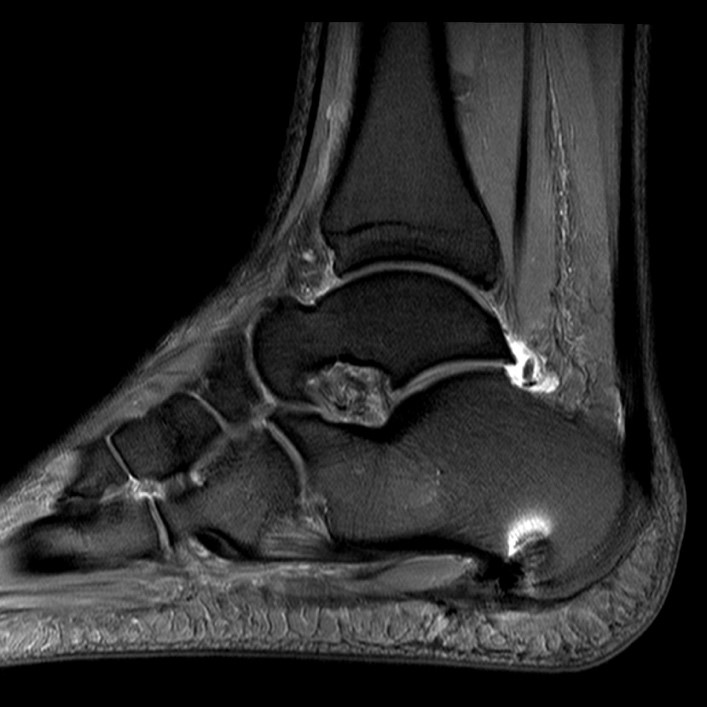

Abb. 2: Teilruptur Plantaraponeurose in der MRT Diagnostik

Eine Teilruptur der Plantaraponeurose kann ursprungsnah oder auch einige cm distal des Ursprungs als Folge einer direkten Gewalteinwirkung auftreten.

Zum Lesen der Bildbeschreibung und zur Vollansicht bitte das Bild anklicken. Bild: Manfred Thomas

In seltenen Fällen findet sich eine komplette Ruptur der Plantaraponeurose als Ursache der Beschwerden (siehe Abb. 3).

Abbildung 3: Komplette Ruptur Plantaraponeurose und Therapie

Kasuistik: Frau, 45 Jahre.

Abb. 3a: Komplette Ruptur der Plantaraponeurose im MRT als Ursache der Beschwerden deutlich erkennbar.

Abb. 3b: Im präop Röntgenbild kein Fersensporn sichtbar.

Abb. 3c: MRT postoperativ, Knochenanker zur Refixation der Plantarfaszie.

Abb. 3d: Röntgenbild postoperativ, Knochenanker zur Refixation der Plantarfaszie.

Zum Lesen der Bildbeschreibung und zur Vollansicht bitte die Bilder anklicken. Bilder: Dr. Manfred Thomas, Augsburg.